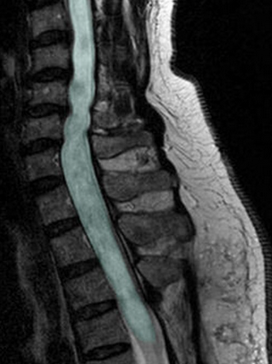

MRI Scan

Diastematomyelia